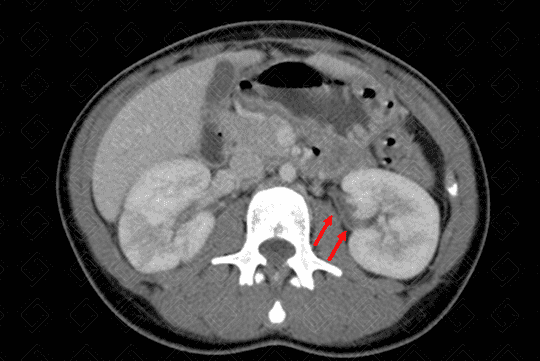

Descrição da lesão: Tomografia computadorizada após a administração do contraste venoso (imagens no plano axial - figuras 1 e 3; e plano coronal - figura 2). Observa-se realce heterogêneo do parênquima renal, com áreas hipocaptantes do meio de contraste venoso (aspecto conhecido como nefrograma estriado).

Há, ainda, lâmina líquida no espaço perirrenal direito (figura 1) e espessamento do urotélio à esquerda (figura 3 - seta vermelha). Estes aspectos são compatíveis com pielonefrite aguda.